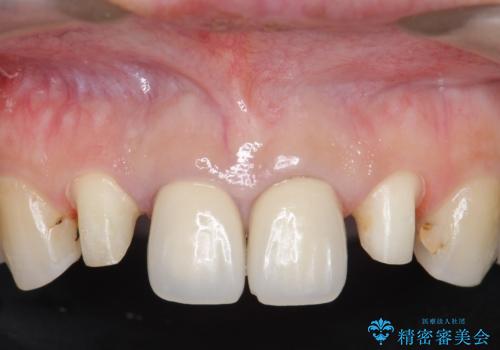

- 上顎の前から2番目の歯の古い樹脂をセラミックにしたいといらっしゃった方の症例です。

古い樹脂を除去後、オールセラミッククラウンによる補綴を行いました。

今回用いたオールセラミッククラウンはジルコニアフレームという白い素材の上にセラミックを盛っているため、審美性が非常に高いのが特徴です。